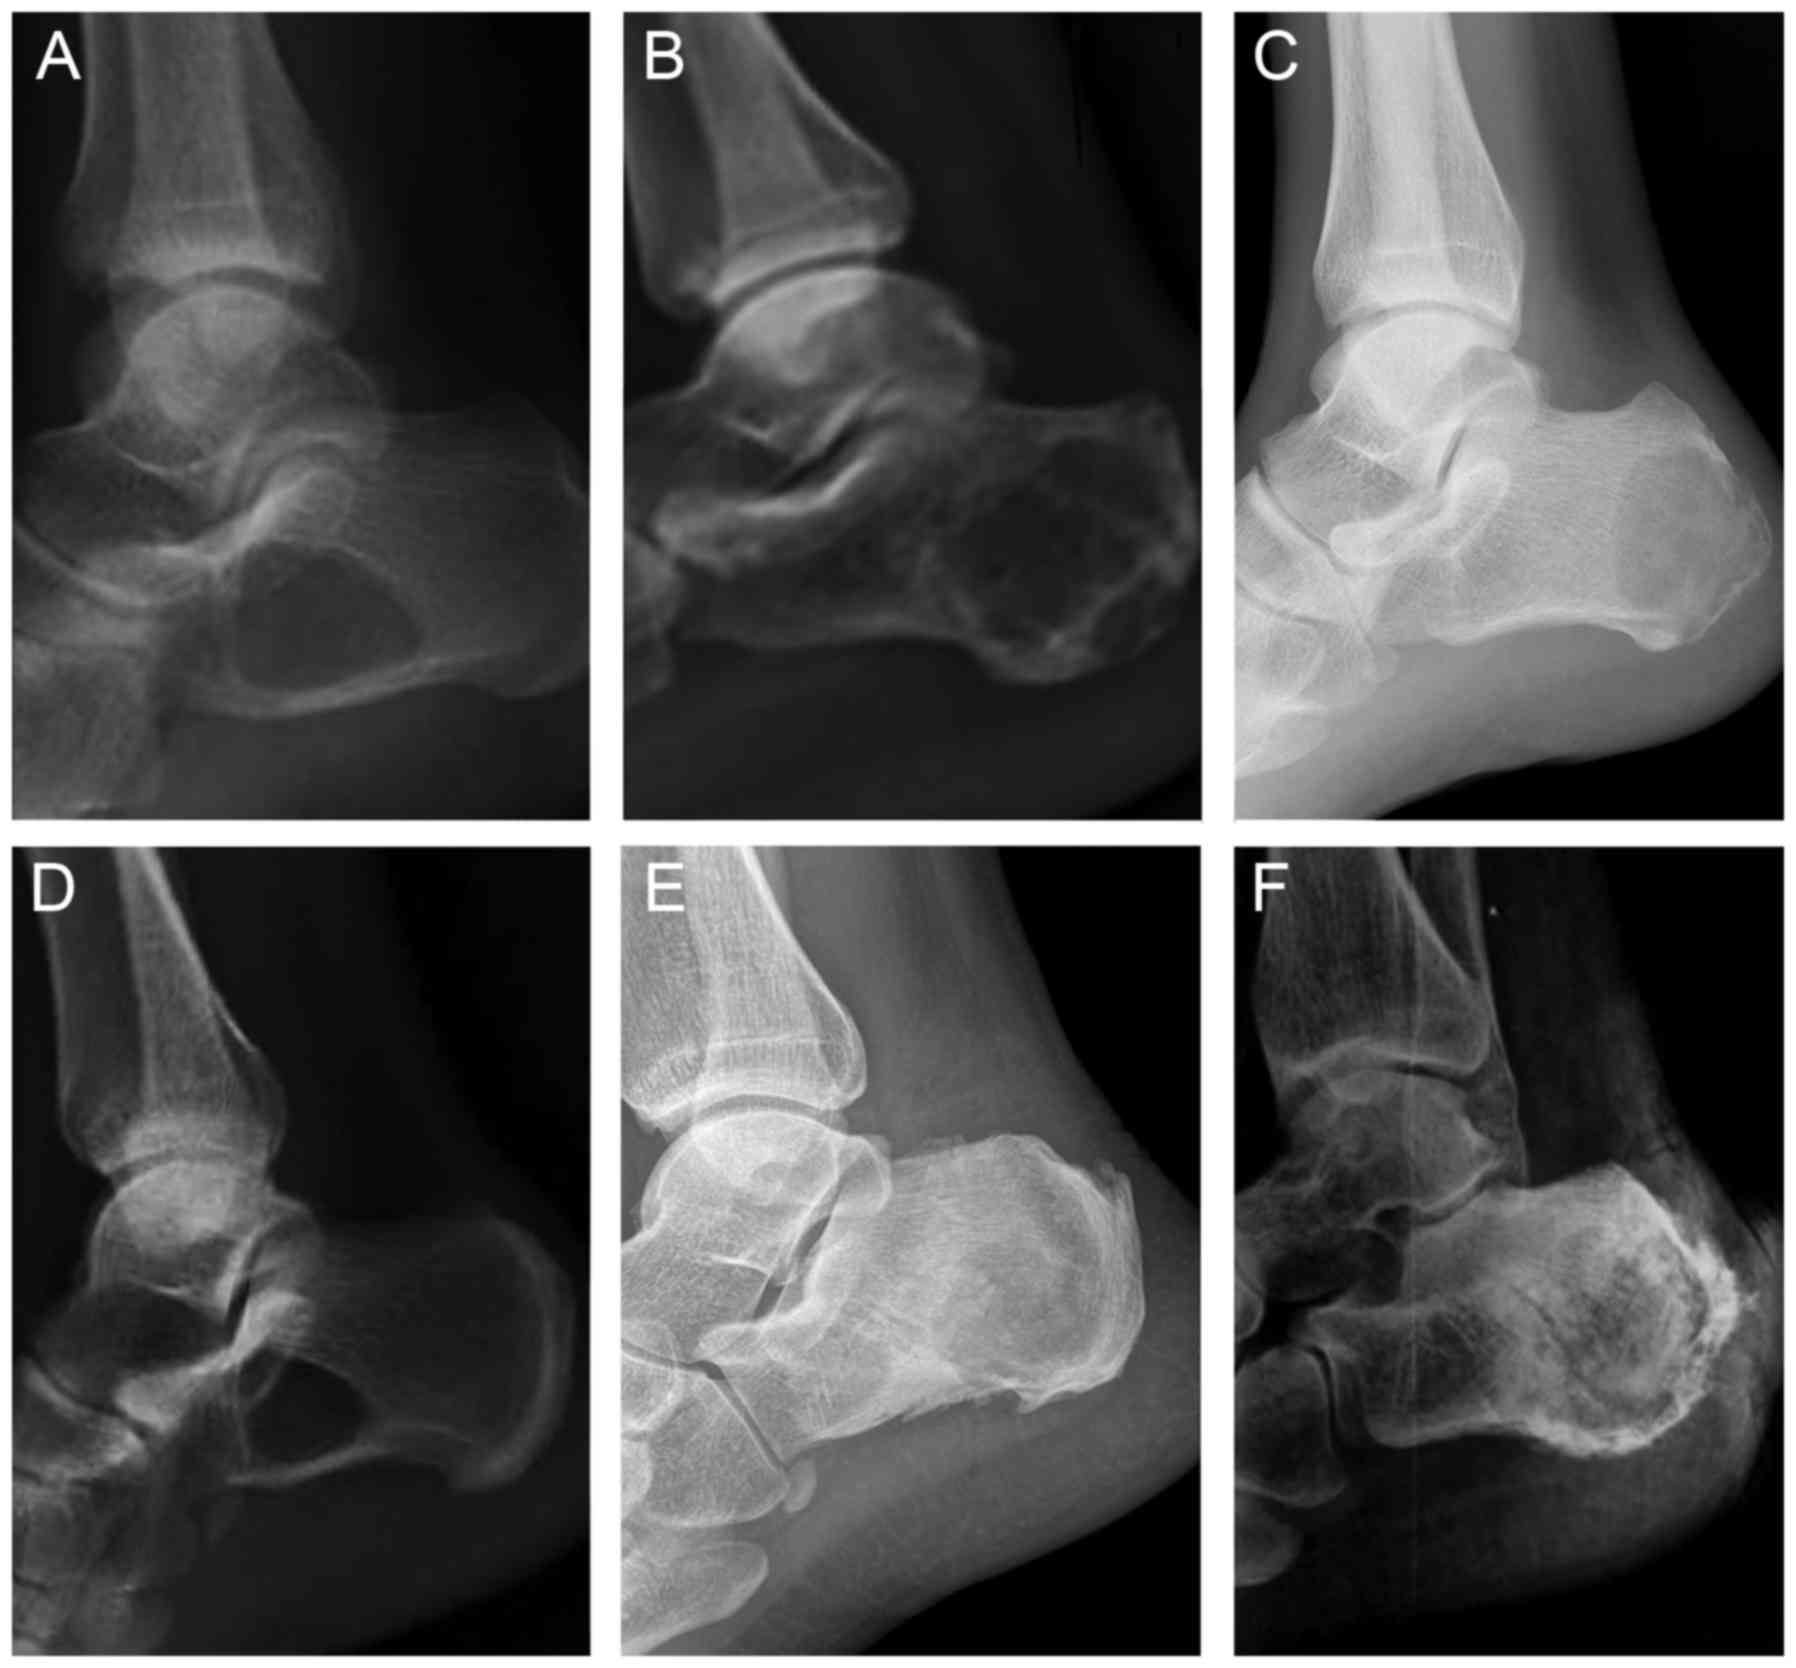

Figure 1.

Lateral x-ray of a number of different calcaneal tumour types. (A) Simple bone cysts of the calcaneus. A solitary, sharply demarcated radiolucent osteolysis may be observed in the calcaneus, without a pathologic fracture. (B) Aneurysmal bone cysts of the calcaneus. The lesion is generally identified as a lytic, expansile lesion with an eccentric shape and septations. (C) Chondroblastoma of the calcaneus. The lesion is located in the posterior calcaneus, which is a lytic expansile mass with a sclerotic margin. (D) Intraosseous lipomas of the calcaneus. A well-circumscribed lytic lesion is located at the base of the calcaneus neck in the region of the Ward's triangle. (E) Chondromyxoid fibroma of the calcaneus. The lesion demonstrates a large lytic lesion with sclerotic margins and ‘soap bubble’ appearance. (F) Chondrosarcoma of the calcaneus. The lesion shows a destructive, expansive and pathologic fracture with calcification of the soft tissues.